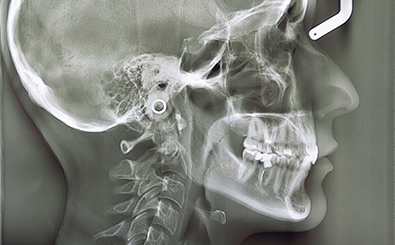

正確な診断を行います

精密機器を導入した検査で、より正確な診断を行っています。これにより、歯や口内状態を詳しく把握し、お子様に合った治療法をご提案することが可能です。診断結果をもとに治療プランをお伝えし、安心して治療を受けていただけるよう心がけています。お口の健康に関するお悩みがあれば、ぜひ当院へご相談ください。

セファロレントゲン

お子様の歯並びや口腔内をしっかり確認するため、セファロレントゲンなどの精密機器や口腔内写真、顔貌写真を用いて精密検査を行います。これらの検査結果をもとに、お子様に合った治療法をご提案し、安心して治療を進められるようしっかりサポートいたします。